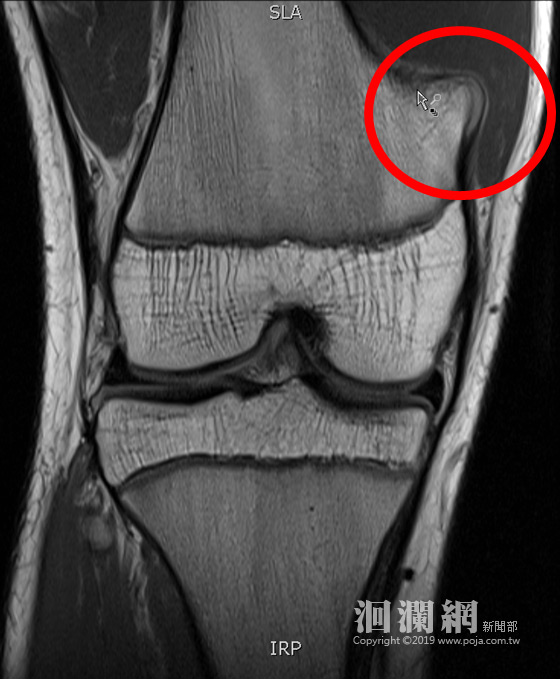

16歲青少年2年前因膝蓋疼痛就醫,診斷為骨軟骨瘤作祟,由於未影響生活,醫師建議先觀察再決定後續是否開刀切除,近日青少年因打籃球引起雙側腳踝疼痛回診就醫,經醫師安排X光檢查後,意外發現原本如乒乓球大小的骨軟骨瘤竟然消失不見。門諾醫院骨科醫師蔡傳恩表示,骨軟骨瘤是一種常見的腫瘤,大多好發在年輕人身上,大部分的骨軟骨瘤會與患者和平共處,但自動消失不見確實罕見。

蔡傳恩說,「骨軟骨瘤」消失在國際上是零星案例,50年間也僅有23篇報告提到自行縮小甚至消失。其消失的原因在假設理論上,有可能是骨骼成熟的過程中,腫瘤融合到生長中的骨骼內部,或是腫瘤遭受外傷甚至骨折,影響腫瘤的血液供應,而推斷少年骨軟骨瘤消失的原因有可能是因為青少年還在長高,骨軟骨瘤被拉平。